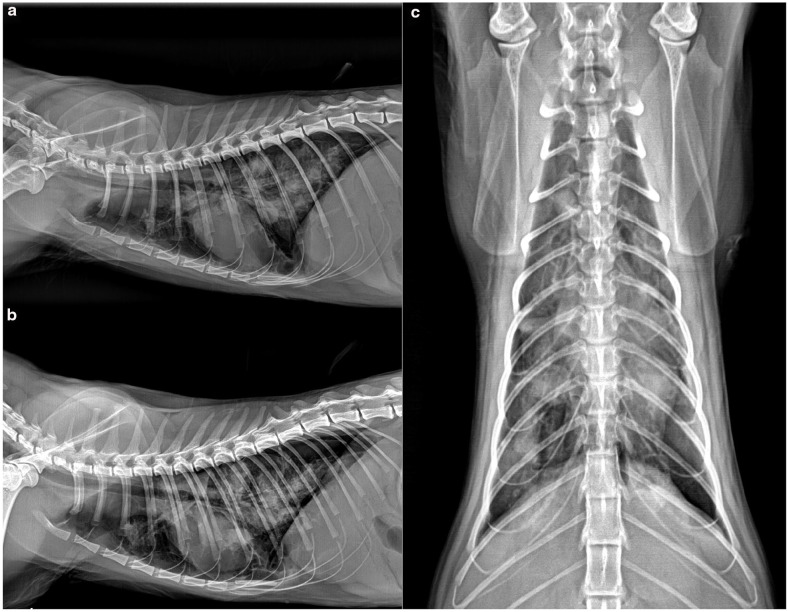

病例总结:一只1岁的完整雌性家养短毛猫,因呼吸窘迫和呼吸急促加重而接受评估。这只猫在4天前被主要临床医生诊断为自发性气胸,并接受了治疗性胸穿刺治疗。在体格检查中,患者表现出肺音减少,呼吸急促和呼吸力度增加。复发性自发性气胸经胸片证实,并重复治疗性胸穿刺。胸穿刺后肺超声显示肺实变、肺结节及多发囊肿样病变,回声壁不规则增厚,中心无回声。胸部重复x线片显示弥漫性中度支气管间质型伴多灶性软组织结节。彻底的粪便检查显示卵子与肺吸虫种类相似,随后的分子分析证实了威氏肺吸虫。猫最初仅用芬苯达唑治疗,结果改善有限,自发性气胸复发。芬苯达唑联合吡喹酮的第二个疗程导致临床改善。这只猫没有任何临床症状,病情很好,在诊断后2年的胸片上没有可识别的肺结节。相关性和新信息:本报告描述了一种新的囊肿样肺超声发现,其特征是回声壁不规则增厚,中心无回声,伴有P westermani感染,表现为复发性自发性气胸。该报告还强调了一种成功的治疗方法,可以长期解决问题。这种新的肺部超声发现的识别有助于早期诊断和治疗猫的肺吸虫感染,特别是对那些出现呼吸窘迫和气胸的猫。

Case summary: A 1-year-old intact female domestic shorthair cat presented for evaluation of worsening respiratory distress and tachypnoea. The cat had been diagnosed with spontaneous pneumothorax 4 days earlier by the primary clinician and treated with therapeutic thoracocentesis. On physical examination, the patient exhibited decreased lung sounds, tachypnoea and increased breathing effort. Recurrent spontaneous pneumothorax was confirmed via thoracic radiography, and therapeutic thoracocentesis was repeated. Lung ultrasound performed after thoracocentesis revealed lung consolidation, pulmonary nodules and multiple cyst-like lesions with irregularly thickened echogenic walls and anechoic centres. Repeat thoracic radiography showed a diffuse moderate bronchointerstitial pattern with multifocal soft tissue nodules. A thorough faecal examination revealed ova resembling those of Paragonimus species, and subsequent molecular analysis confirmed Paragonimus westermani. The cat was initially treated with fenbendazole alone, which resulted in limited improvement and recurrent spontaneous pneumothorax. A second course of fenbendazole combined with praziquantel led to clinical improvement. The cat remained free of clinical signs and was doing well, with no identifiable lung nodules on thoracic radiography 2 years after diagnosis.